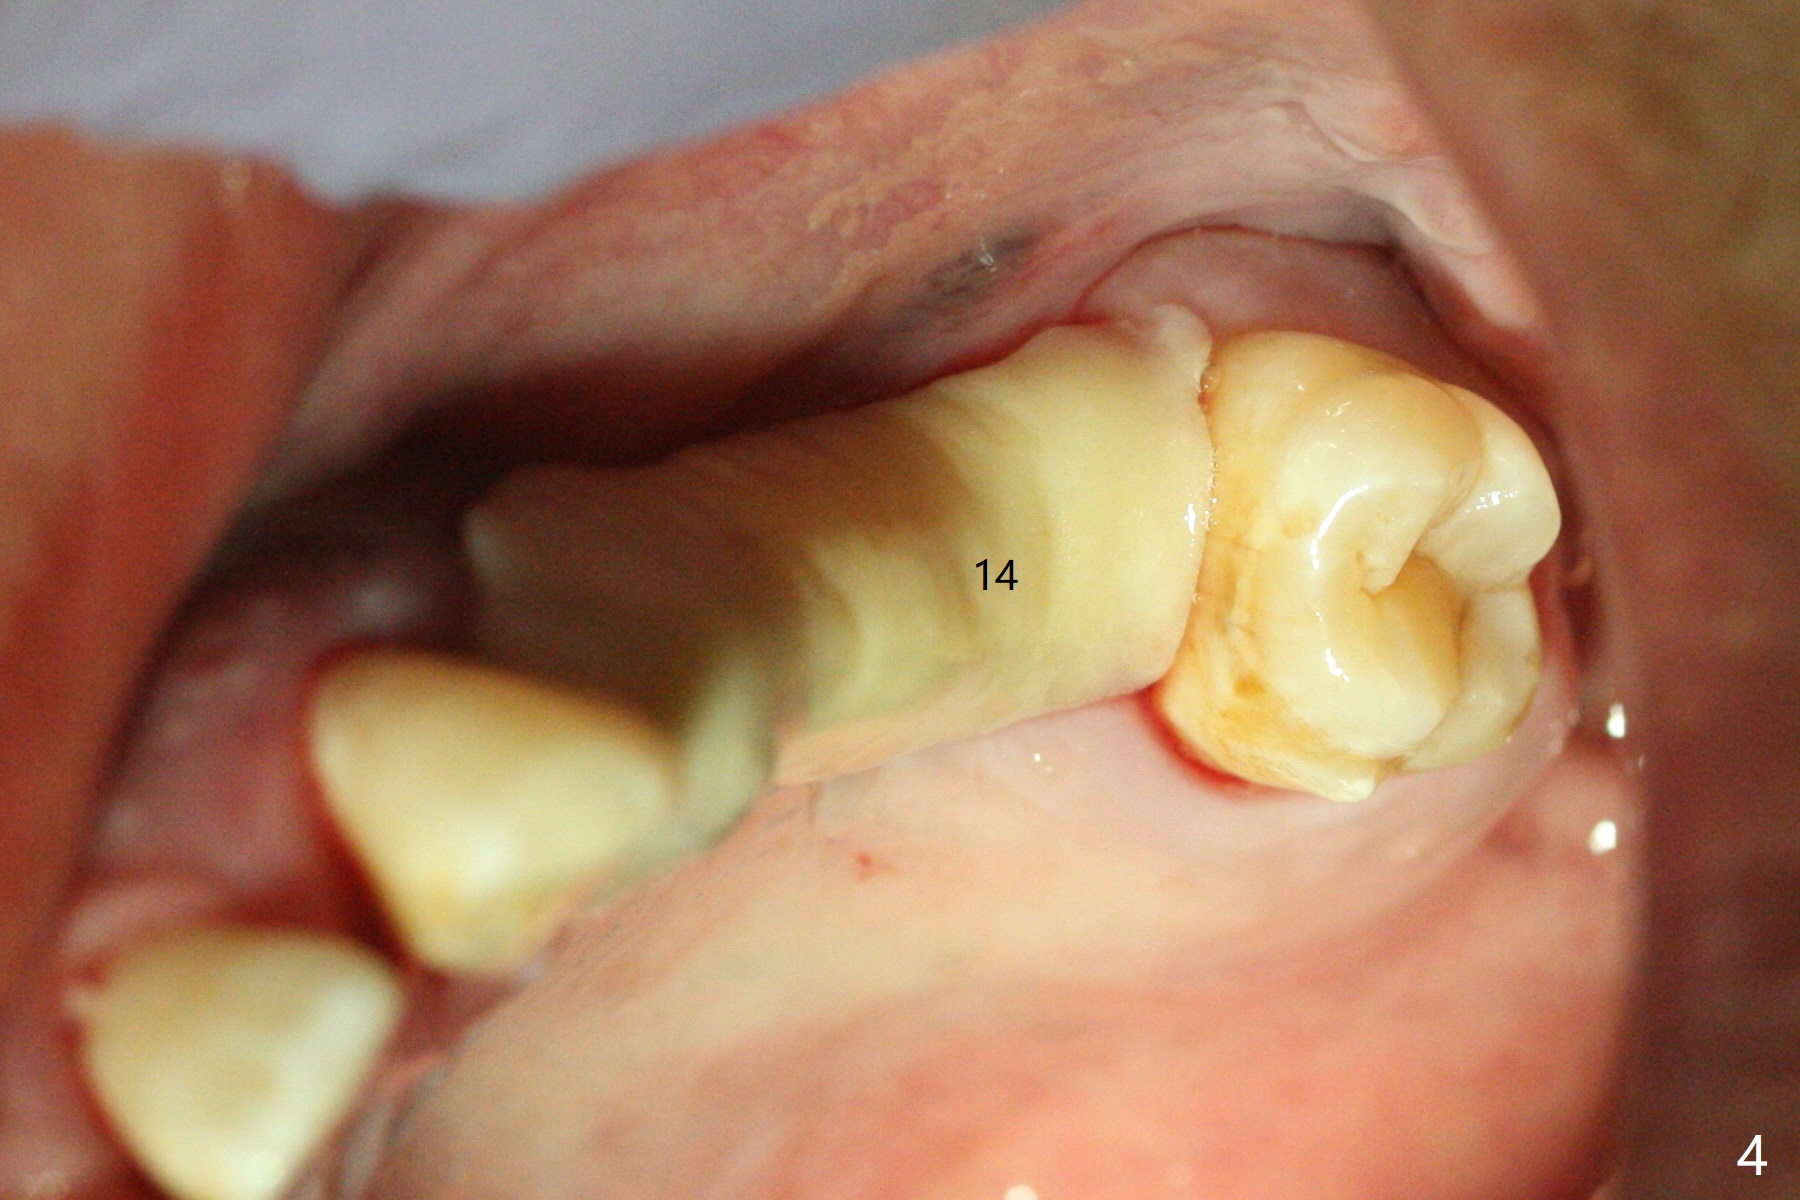

Immediate placement at #12 is smooth with 20 Ncm, whereas delayed one at #14 involves sinus membrane perforation; after insertion of PRF and mixture of autogenous bone and allograft, a shorter dummy implant tries in with stability (Fig.1). The final implant at #14 has ~60 Ncm, but the coronal palatal bone may be insuficient (Fig.2). Sticky bone is placed to bury the implant at #14 (Fig.3 *). After placement (incomplete, Fig.3 <) of a 4.5x7.5(4) mm pair abutment, setting acrylic is applied around the abutment, over the bone graft at #14 (to prevent loss) and pressed into the undercuts of the proximal surfaces of the neighboring teeth for retention (Fig.4). The sockets at #12 heals 8 days postop when a 2nd acrylic dressing dislodges (Fig.5). It appears that the retention of 3-unit acrylic dressing is poor. The wound at #14 also heals, but it would be better to make an incision to save the soft tissue (Fig.6). The bone/implant gap reduces at #13 five months postop (Fig.7 (complete abutment seating)). There is no implant thread exposure at #13 (immediate), while minor exposure mesial to #15 (delayed). The patient complains of food impaction between #13 and 14 buccally 6 months post cementation (Fig.8). Return to Upper Molar Immediate Implant, No Deviation 19 Next Case Xin Wei, DDS, PhD, MS 1st edition 01/21/2020, last revision 02/03/2021